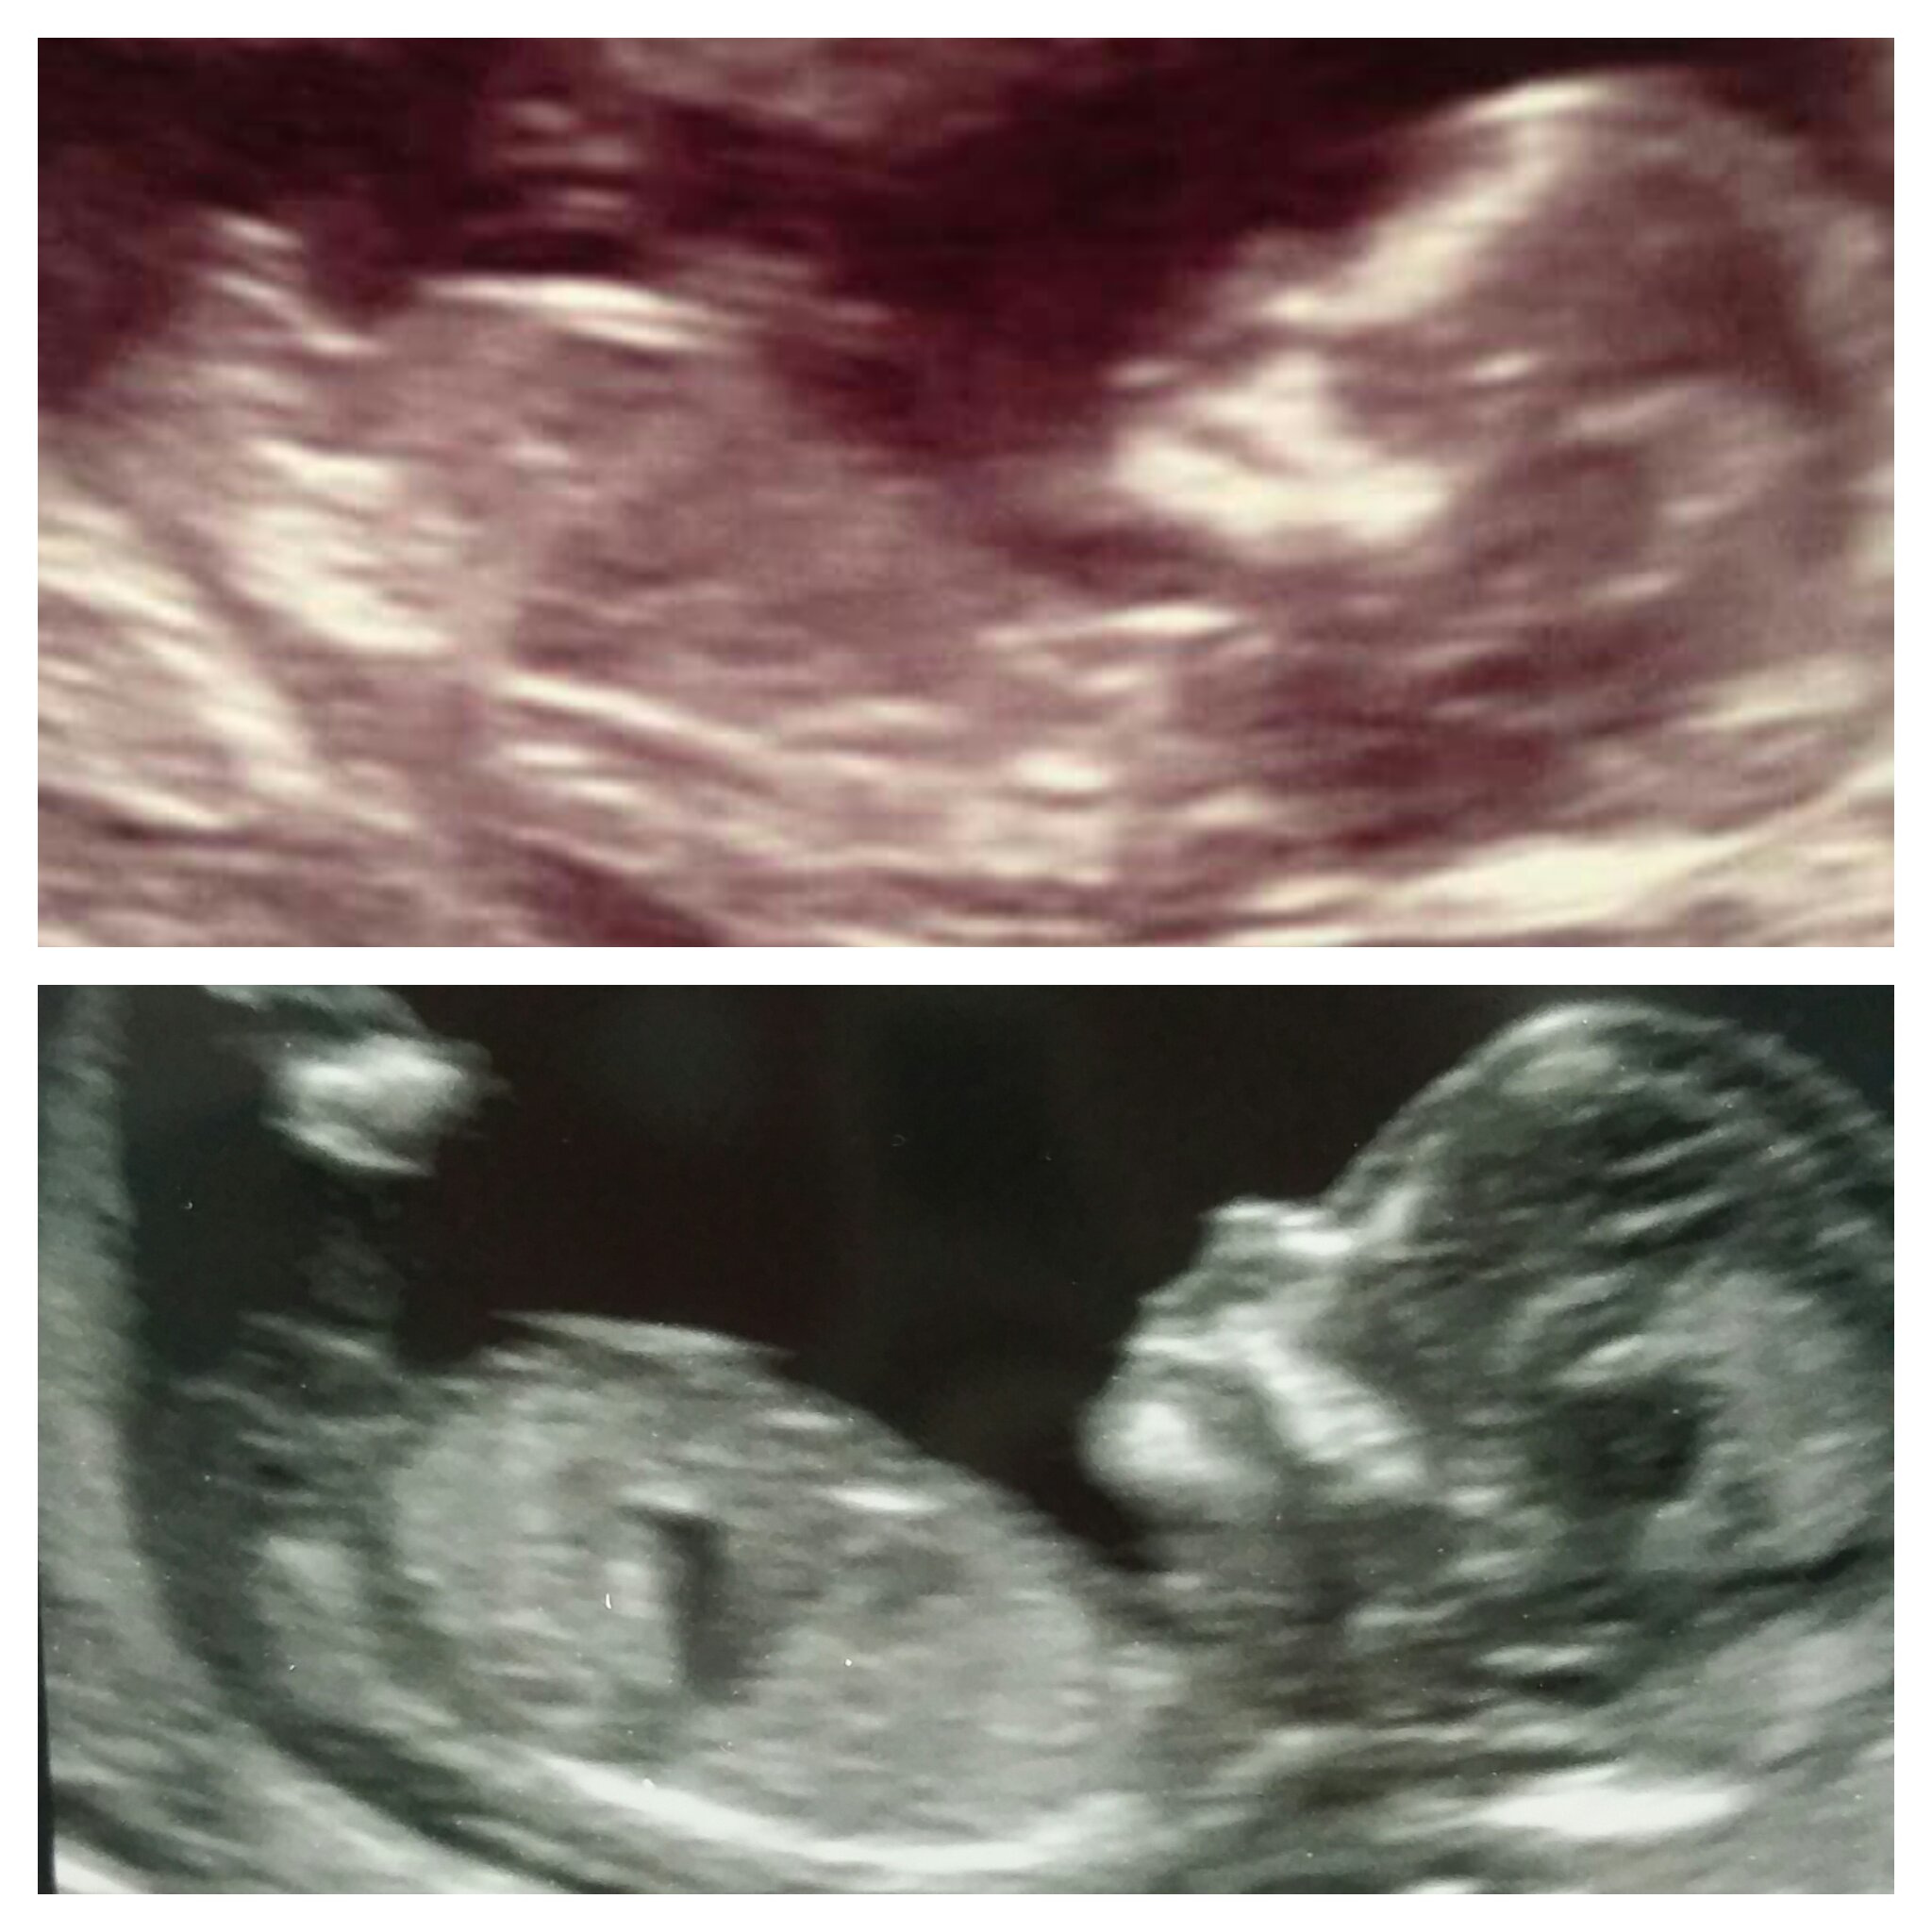

Hi all I'm new here but looking for your help. Had my scan today 13 weeks and 3 days. Do you think boy or girl? My first born is the top one and new one at the bottom can you guess both? :) xxxxxAttachment 28649

They both look very similar..just a guess I would say girls, x

Top one boy. Bottom one boy lean

Top one Boy, Bottom one looks boy too I think..?

Top one is all boy. Boy lean for the bottom pic, but not totally clear.

Top one was boy

boy and girl from me

Top boy, bottom girl

Top boy not sure abt bottom but would lean girl

Top is a boy. Bottom is not the best pic but guessing girl. Congrats!

Oh it seems very mixed boy or girl my first born was a boy!! And everyone was right!!! Just so intriged as to what gender my little bun in the oven will be this time xxxxxxxxx